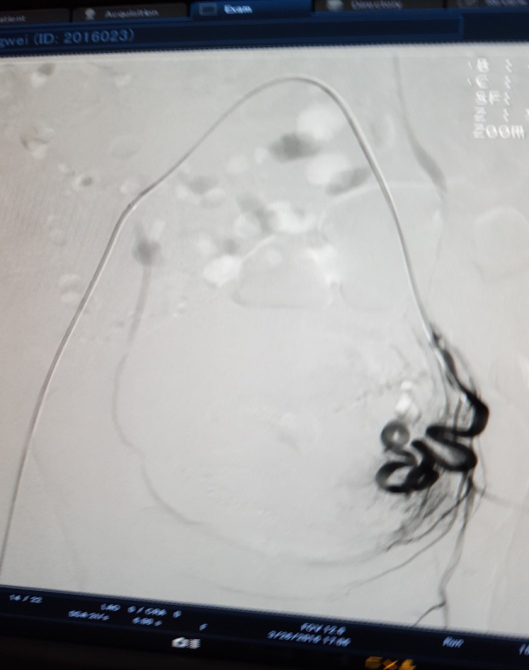

治疗前 右侧                            治疗后 右侧分支血管消失

3月28日下午3点,在医院新导管室内,放射介入科主任张敏荣与任长德、李可峰医师成功地完成了新导管室建成后首例子宫腺肌症介入手术。该患者女性、40岁,因患子宫腺肌症,造成腹痛难耐,C臂下造影见:左子宫动脉增粗,分支数量增多、迂曲,用PVA颗粒栓塞迂曲的分支动脉,在妇产科保驾下,手术操作顺利。经过几天的对症治疗,各项检查指标符合出院标准,现病人已出院家中休养。该项手术的成功开展,又一次填补了市中医院该项之空白。